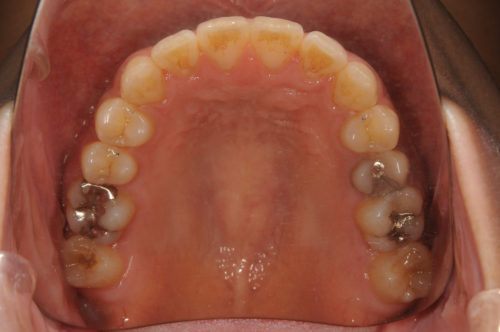

銀歯の下がむし歯になっており神経をとる治療になるため、左右第二大臼歯を抜歯してうまっている親知らず(智歯)を使用。第二大臼歯に智歯(親知らず)を使用しているため非抜歯治療と同様の矯正治療計画。

治療前